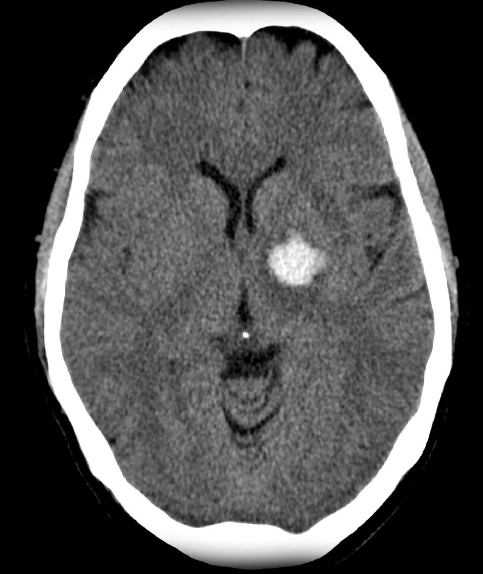

Intracerebral hemorrhage

Infarction appear hypodense on CT without contrast

Sign? Hyperdense sign in stroke; LT Middle cerebral artery hyperintense

Y

Dense basilar artery and middle cerebral arteries on CT

Thrombus in vessel is hyperdense relative to flowing blood